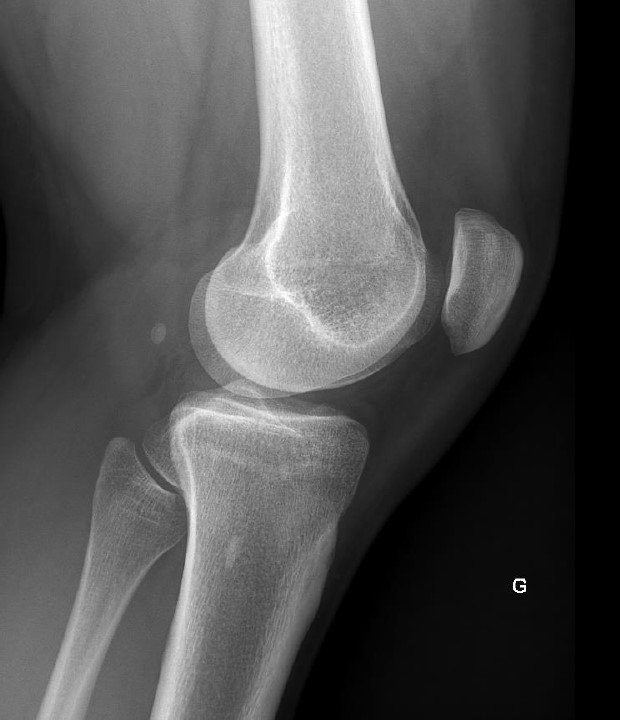

L'angle mort du genou